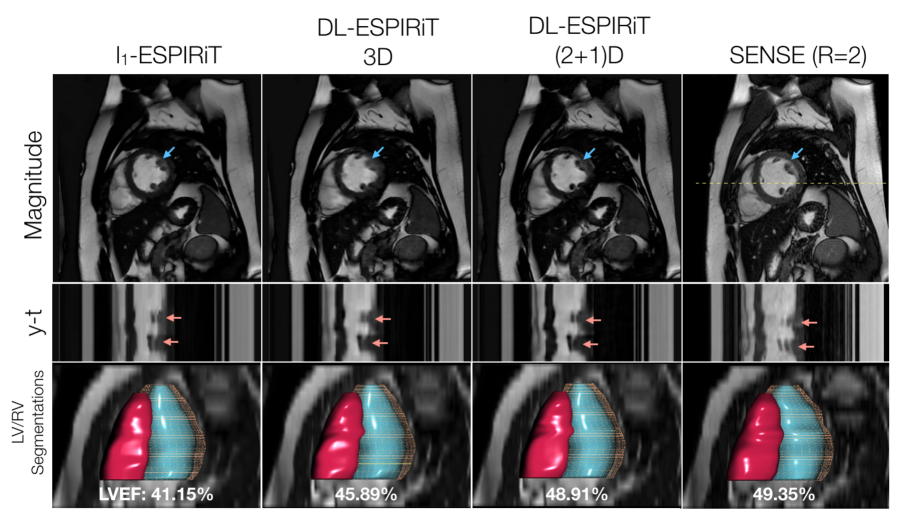

To demonstrate the generalizability of the proposed approach, Figure 9 shows l1subscript𝑙1l_{1}-ESPIRiT and DL-ESPIRiT reconstructions of a prospectively undersampled dataset acquired in a patient with an abnormal heartbeat. Despite the lack of this type of cardiac motion in the training data, DL-ESPIRiT faithfully reconstructs the abnormal behavior when compared to the images from the clinical standard sequence. Corresponding videos of each reconstruction are shown in Supporting Information Video S6.

Figure 9: With IRB approval, two prospectively undersampled 2D cardiac cine scans are performed in a pediatric patient with premature ventricular contractions (PVC), which manifest as an extra beat motion during the cardiac cycle. Performed as part of a routine cardiac MR exam, the first acquisition is uniformly undersampled (R=2) and reconstructed using SENSE. The second acquisition is undersampled using a variable-density k-t sampling pattern (R=12) and is reconstructed using l1subscript𝑙1l_{1}-ESPIRiT and DL-ESPIRiT algorithms. Mid-systolic frames, y-t profiles, and segmentations of the left and right ventricles are shown here. Despite the lack of subjects with PVC in the training data, the DL-ESPIRiT network is able to generalize to this particular example and reconstruct an accurate depiction of the extra beat motion that agrees with both l1subscript𝑙1l_{1}-ESPIRiT and SENSE reconstructions (red arrows). Furthermore, left ventricular ejection fraction (LVEF) is measured in each of the reconstructions, and it is shown that (2+1)DM2 DL-ESPIRiT is in better agreement with the clinical standard SENSE reconstruction than is l1subscript𝑙1l_{1}-ESPIRiT and 3DM2 DL-ESPIRiT. Corresponding videos for each reconstruction are shown in Supporting Information Video S6.